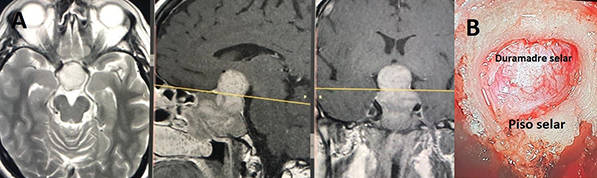

Figura 1: A - Resonancia magnética preoperatoria y B - foto intraoperatoria)

Se examinó previamente una TC de cortes finos de los senos paranasales para variaciones importantes tales como el seno esfenoidal no neumatizado, deformidad nasal, y patrón de septación del seno esfenoidal. 8-13